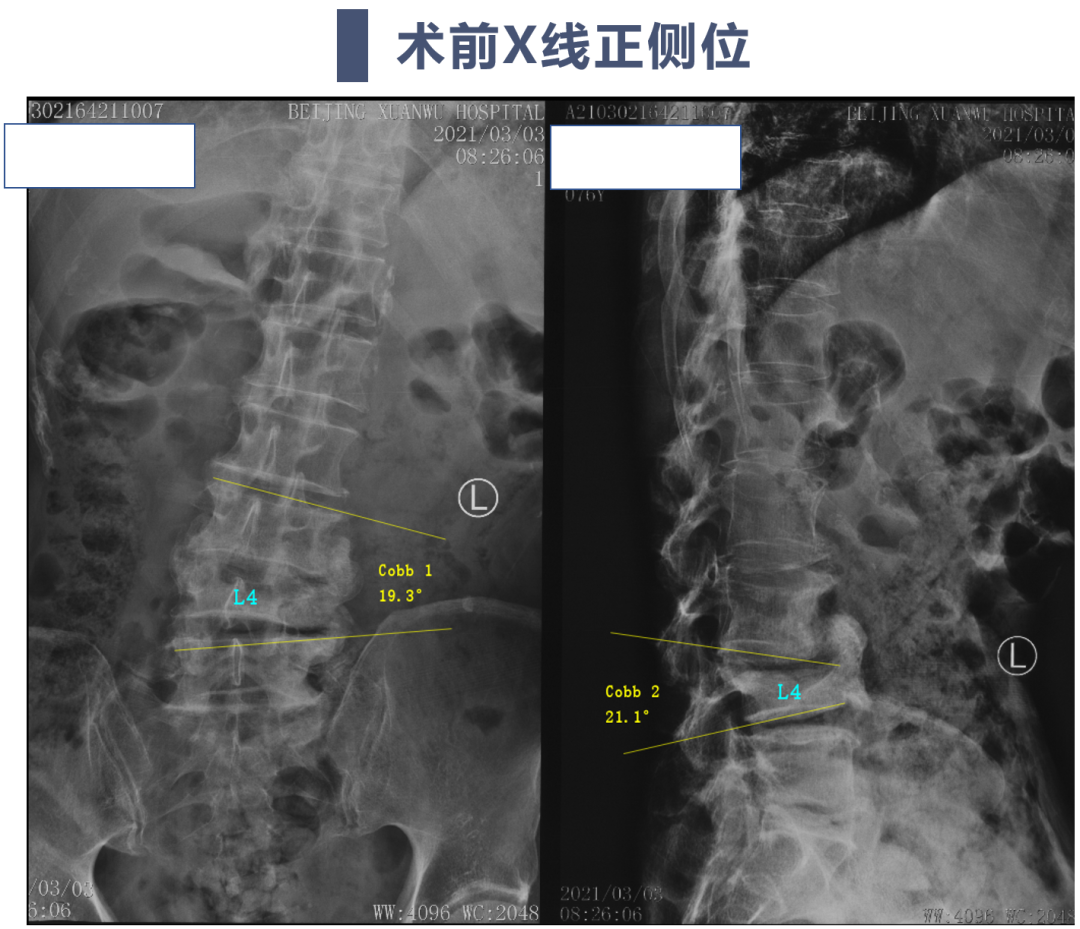

讨论主题:L4压缩骨折伴脊柱侧后凸畸形

影像资料:

腰椎侧后凸畸形

腰椎陈旧性压缩性骨折(L4)